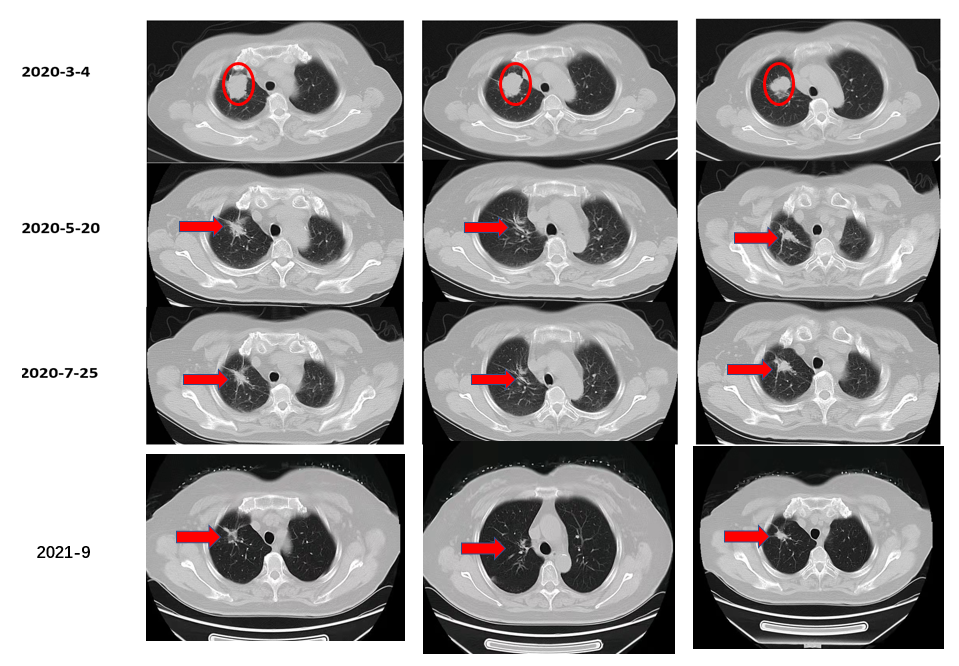

治疗前基线:右肺上叶多发结节,大者(2.3*2.0*2.1cm)考虑恶性。

治疗2月后:(SD)右肺上叶多发结节,大者(2.0*1.5*1.8cm)恶性可能性大。

治疗8月后:(PR)右肺上叶多发结节,大者(1.2*1.1cm)较前明显缩小。

治疗13个月后(2021-8):(PR)